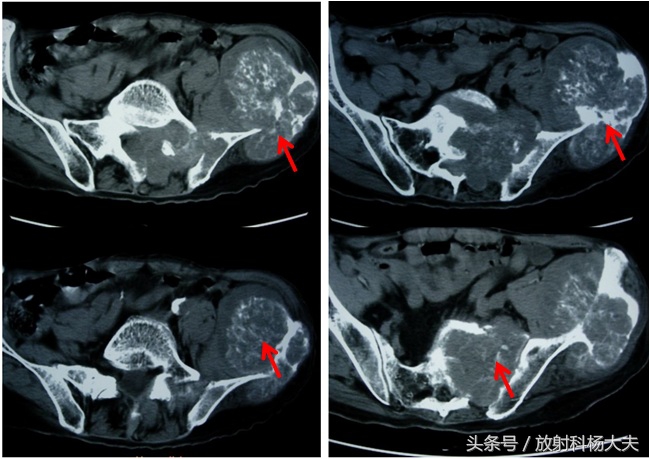

近1年来刘叔左髂腰部肿物增大明显,并伴有行走时间较长后左髂腰部酸胀感,近半年来刘叔出现了腰骶部疼痛的症状。一个月前,刘叔来我院检查,骨科医生要求刘叔做一个骨盆CT检查,骨盆CT检查发现左髂骨翼及左骶髂关节多发骨质破坏并软组织肿胀形成,其内可见不规则高密度灶。影像诊断考虑为左髂骨软骨肉瘤。一周前刘叔做了穿刺活检,活检结果是软骨肉瘤。